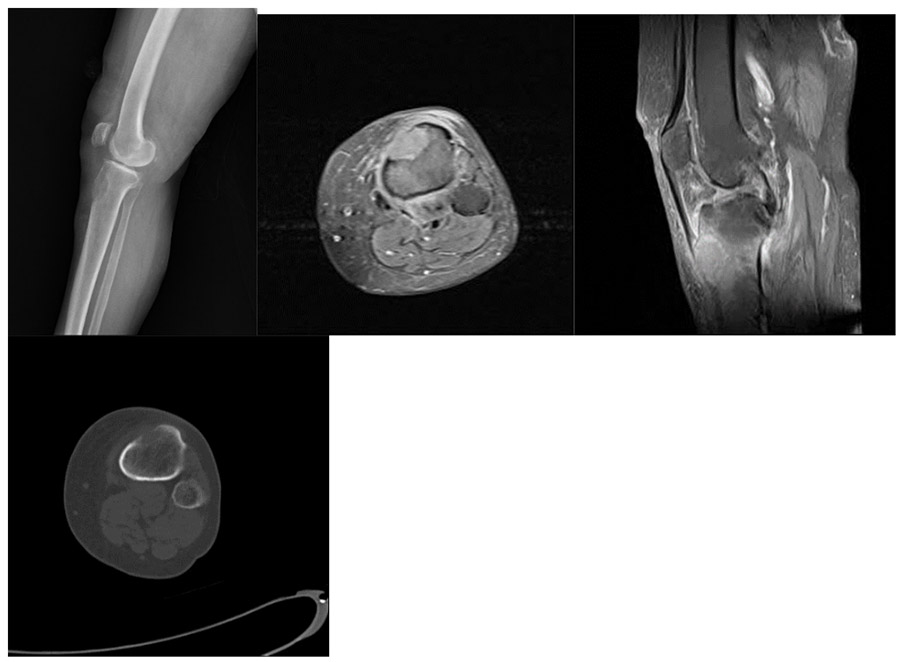

CASE 47: Cervical cancer metastasis to the upper end of the left tibia.

Before the surgery: X-ray and CT scans show necrosis in the anterior portion of the upper end of the tibia, while MRI shows tumor tissue and surrounding edema in the same area.